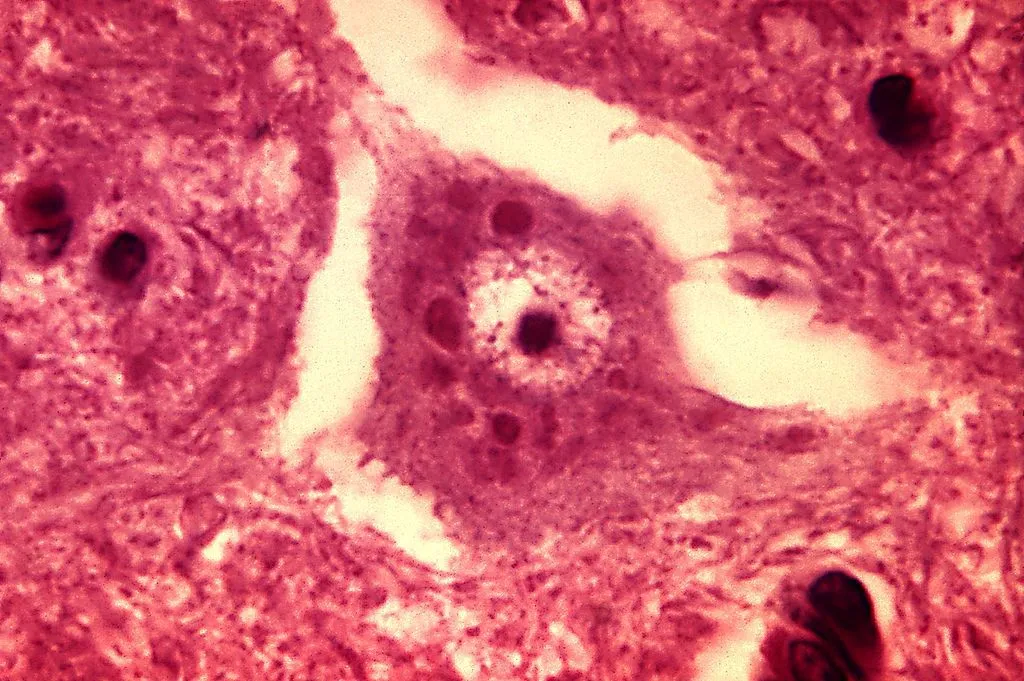

The rabies virus, replicating in the brain, infects neurons. The patient develops encephalitis, which is when the brain is inflamed. The later-stage symptoms that we associate with rabies—aggression, hyperactivity, and hydrophobia, appear now.

There is a lot we still don’t know about rabies. We know that the virus invades neurons and makes its way to the brain. We also know how the brain looks after an invasion, but the exact mechanism of how a virus goes about infecting the brain. We’re still investigating which parts of the brain the virus targets, and that leads to the disease’s unique symptoms.